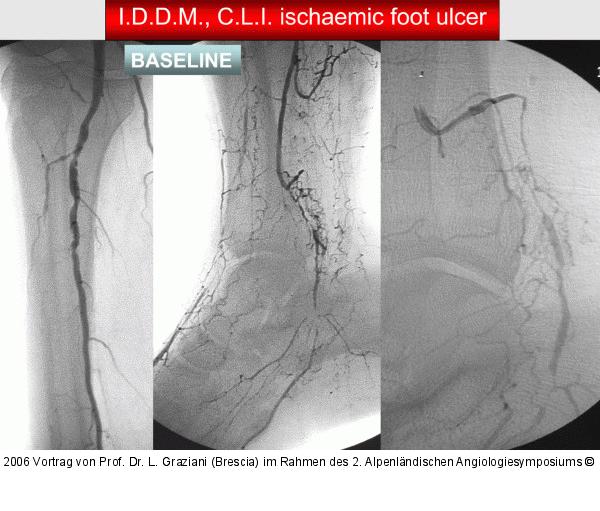

Abbildung 74: Arteria dorsalis pedis - Katheterisation

Arteria dorsalis pedis - Katheterisation